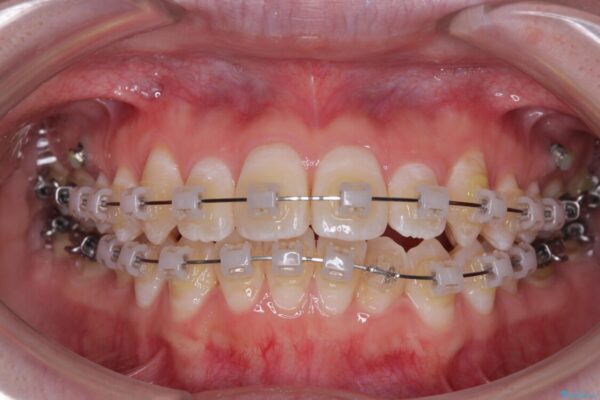

マウスピース矯正も検討されていましたが、「装着時間の自己管理が難しそう」「なるべく早く治療を終えたい」とのご希望から、ワイヤー矯正を選択されました。

目立ちにくさと費用のバランスを考慮し、プラスチックブラケット+メタルワイヤーを採用。日常生活でも装置の存在感を気にせずお過ごしいただけます。

治療途中

• 【モニター】前歯のデコボコをスッキリ解消!目立ちにくいワイヤー矯正でスピーディに治療完了 治療途中画像